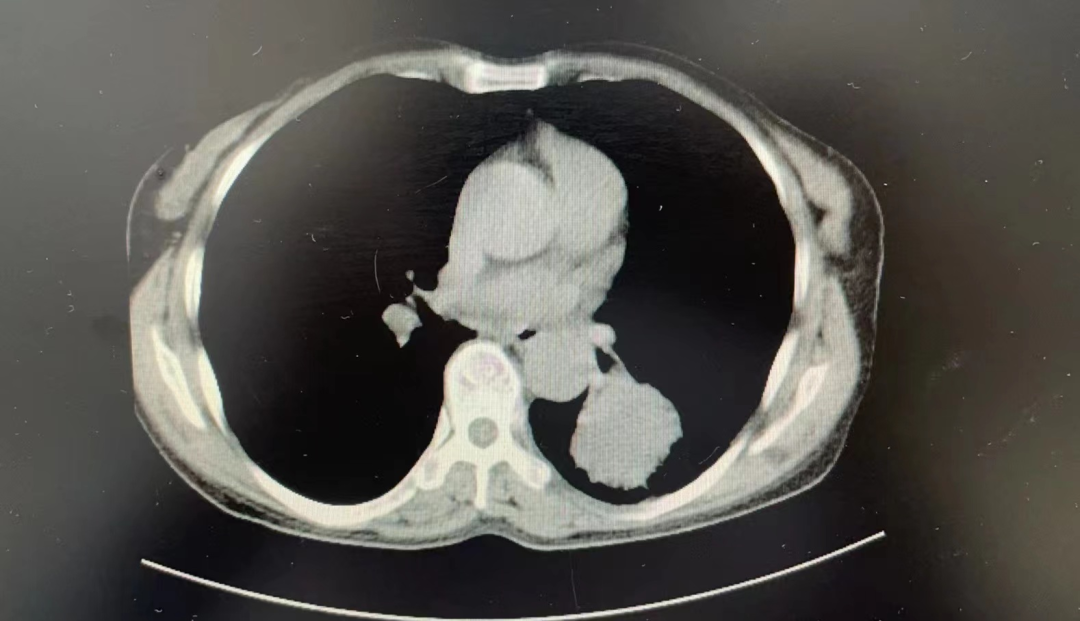

2023年10月上旬,丽江市人民医院呼吸与危重症医学科副主任白成剑、主治医师谭行俊为一“肺部占位”患者成功开展了国家呼吸内镜技术规范认定的四级手术(新技术、新项目)—支气管镜下冷冻技术(包括冷冻肺活检、冷冻止血、冷冻治疗)。

支气管镜下冷冻技术是一种通过低温破坏病变组织结构的方法,达到止血、冻取病理及治疗的技术方案,,这一技术相对传统活检钳钳夹、穿刺活检,可有效避免疼痛、出血多、并发症多、病理组织少、病理组织裂解等缺点,可兼顾诊断及治疗。且在国内外应用成熟、安全、有效。

这是丽江市人民医院呼吸与危重症医学科首次进行支气管镜下冷冻技术的手术。该技术主要用于肺部占位病变的诊断和治疗,具有创伤小、恢复快、疗效好等优点。

在手术中,医生使用支气管镜将冷冻探头引入患者的支气管内,通过冷冻作用可以破坏肿瘤细胞、止血、减少病变范围,同时还可以获取组织标本进行病理学检查。

这是丽江市人民医院呼吸与危重症医学科首次开展内镜四级手术,即支气管镜下冷冻技术。该技术被国家呼吸内镜技术规范认定为四级手术,属于新技术和新项目。在本次手术中,副主任白成剑和主治医师谭行俊成功地为一名患有肺部占位的患者进行了支气管镜下冷冻技术,包括冷冻肺活检、冷冻止血和冷冻治疗等步骤。